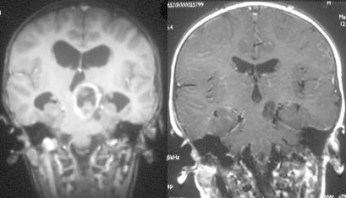

il peut s’agir d’une lésion dysplasique (augmentation de volume diffuse, sans prise de contraste, qui ne progresse pas) ou d’un gliome de bas grade (le plus souvent pilocytique) : c’est donc l’évolution qui permet de distinguer ces deux types de lésion.

il se révèle par une hydrocéphalie obstructive, que l’on traite par endoscopie ; quant à la tumeur, on se contente le plus souvent de la surveiller, elle progresse rarement. on discute alors de biopsies puis d’un traitement par chimiothérapie, voire radiothérapie. ces lésions nécessitent parfois une exérèse : selon la topographie, médiane ou latérale, on abordera ces lésions par une voie d’abord de la région pinéale ou une voie latérale sous-temporale

l’astrocytome bulbo-médullaire

c’est le plus souvent un astrocytome pilocytique, parfois un gangliogliome. il se révèle de façon lentement évolutive par des signes d’atteinte des voies longues, des nerfs mixtes, des symptômes cérébelleux. parfois, il existe une anorexie avec retard pondéral majeur réalisant un syndrome de Russell (cachexie pseudo-diencéphalique).

il peut être bien limité, en particulier avec des kystes ; il nécessite alors souvent un traitement chirurgical.